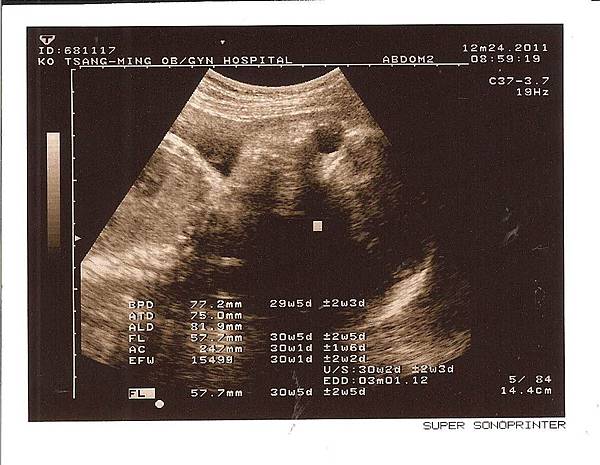

現在頭的寬度(BPD) 為 77.2 mm( 上個月: 65.8 mm)

腹圍(AC) 為 247 mm (上個月: 195 mm)

大腿骨長度(FL) 為 57.7 mm(上個月: 47.2 mm)

本周新增體重數值 為 1549 g (上個月: 838 g)

他說" 羊水的量正常 小孩大小正常 胎盤位置正常 子宮頸正常 很好!! "